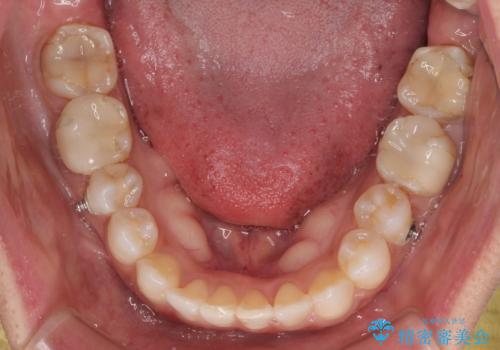

咬合力が非常に強く、治療が進むにつれて上下奥歯が離開してくることが予想されるため、治療途中から上下の顎間ゴムを使用することを理解いただき、インビザラインによる矯正治療を行うこととしました。

咬合力による臼歯離開は顎間ゴムで改善されましたが、それとは別に下顎小臼歯がマウスピースに追従せず、補正のためのゴムかけが必要となりました。

大変なゴムかけ作業を頑張っていただき、無事に治療を終えることができました。